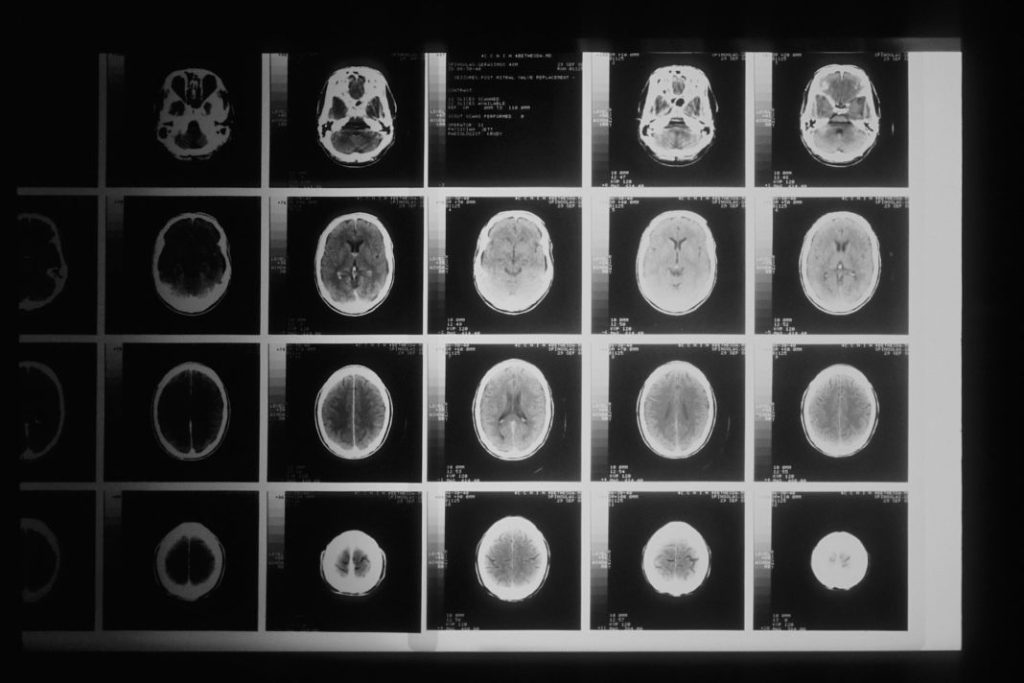

Se conoce una afección que produce una interrupción del flujo sanguíneo a una zona del cerebro. Esto lo puedes comparar perfectamente con un infarto al corazón, pero en este caso estamos hablando de una lesión que se ubica en el cerebro.

Según el cuadro clínico que se presente, puede entonces hablarse de accidente cerebrovascular, embolia, infarto cerebral o apoplejía. Básicamente, hay dos tipos de ictus y cada uno de ellos tiene una causa diferente.